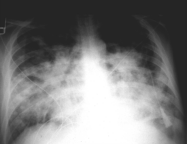

Severe Acute Respiratory Syndrome (SARS Virus),

| This page is dedicated to Severe Acute Respiratory Syndrome (SARS). It was setup as a result of the recent outbreak in Canada, China, Hong Kong Special Administrative Region of China, Indonesia, Philippines, Singapore, Thailand, and Vietnam. This page will be updated when information is available. You are welcome to suggest links or comments related to this site by e-mailing directly to me at cyberdoc@outlook.com. I however have the right to moderate these links. Initial news indicated it may belong to a paramyxovirus group and the latest news now confirms it is a new Coronavirus. Please read the disclaimer.